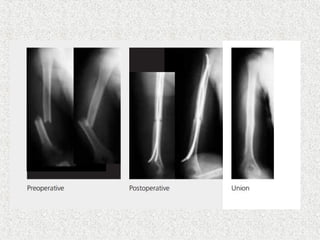

 Closed unstable#  Irreducible #  Polytrauma  Always descending technique  Medial & lateral of tibial tuberosity  Nail tip curved posteriorely-antecurvation